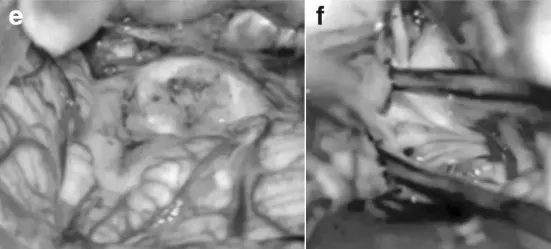

不久后,小A被推入手术室。这一次他们找到的主刀正是前期了解过的巴特朗菲教授。在术中磁共振系统的辅助下,巴教授为小A进行了俯卧位手术。

巴教授通过后正中位和左侧枕下颅骨切开术暴露肿瘤,使用CUSA刀切除肿瘤,在左侧外侧隐窝,肿瘤基底黏连颅神经根部,术中小心地将肿瘤与颅神经成功分离。同时,巴教授在处理后组颅神经时非常小心,主要是为了保护吞咽功能。最终,颅神经成功保留,尤其是第九、十、十一颅神经保护良好。

最终,手术果然如小A父母预期那样,肿瘤获得全切,小A无任何神经损伤。术后两周,小A吞咽困难、脱水、头部倾斜等症状均得到恢复;术后3年,随访显示全切肿瘤,小A处于良好的临床状态,无神经功能缺损。照片中,小A穿着衬衫领结,已长成更加挺拔的阳光男孩,一家人挥别过去的阴霾,携手共赴新生活。